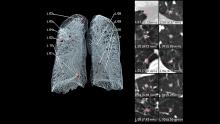

Researchers using fluorodeoxyglucose (FDG)-positron emission tomography (PET) have found increased FDG uptake in the lymph nodes of patients 7-10 weeks past their second mRNA-based Pfizer-BioNTech COVID-19 vaccination. This new information indicates a persistent immune response that could be mistaken on imaging exams for serious conditions like lymphoma over a much longer period of time.

Recent recommendations for post-vaccine lymphadenopathy advise scheduling routine imaging, such as screening mammography, before, or at least 6 weeks after, the final vaccination dose to eliminate false positive results. However, this new research showed that avid axillary lymph node uptake was present beyond 6 weeks after the second vaccination in more than 29% of the patients in the study cohort.

The authors stated “This study shows that avid axillary lymph node uptake on FDG PET/CT can be detected in more than a quarter of our patient population even beyond 6 weeks after the second dose of the mRNA-based COVID-19 vaccination. Compared to a previous study showing normalization of FDG uptake within 40 days of receiving an inactivated H1N1 influenza vaccine, we found uptake persistence even at 70 days. Physicians should be aware of this potential pitfall.”

Some images in this video are from another Radiology study, which showed PET tracer uptake at the COVID vaccine injection site and other examples of axillary adenopathy.[3]